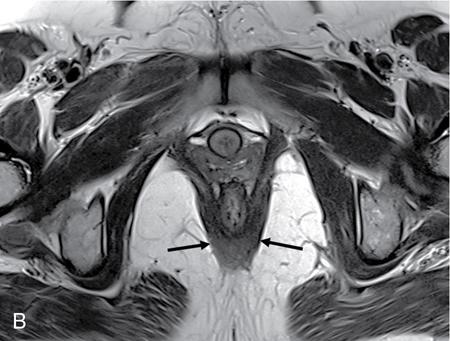

PELVIC FLOOR IMAGING – ANTERIOR AND MIDDLE COMPARTMENTS Anu Epean, Deepa Korula The term ‘Pelvic floor disorder’ refers to dysfunction of the pelvic floor musculature and connective tissues which provide support for the pelvic organs. This can produce a wide range of symptoms such a urinary incontinence, straining to void, dyspareunia, constipation, faecal incontinence and organ prolapse. The greatest risk factors for pelvic floor disorders are female sex and advanced age. Other risk factors include obesity, pregnancy, multiparity, smoking, connective tissue disorders. The pelvic floor is broadly divided into three compartments. The bladder and urethra form the anterior compartment. The vagina and uterus form the middle compartment and the posterior compartment comprises of the rectum and anal canal (Fig. 7.16.1.1). The attachment of the fascia, muscles and the ligaments to the bony pelvis form the support for these structures. From cranial to caudal, there are three layers which make up the pelvic floor – the endopelvic fascia, the pelvic diaphragm and urogenital diaphragm. This is the most cranial layer of pelvic floor, lying deep to peritoneum. It is a fine structure, comprising of a network of connective tissue which encases the pelvic viscera, provides support to the pelvic organs and maintains their anatomic relationship. There are several condensations of this fascia and ligaments which provide support in each of the pelvic compartments. In the anterior compartment, a fascial condensation called pubocervical fascia extends from anterior vaginal wall to the pubis. Tear in the pubocervical fascia can cause cystocele and urinary incontinence. There are three groups of ligaments which provide urethral support – periurethral, paraurethral and pubourethral ligaments. The periurethral ligaments arise from medial fibres of pubococcygeus and pass ventral to urethra. The paraurethral ligaments connect the lateral wall of urethra to periurethral ligament and pubourethral ligament connects the lateral wall of urethra to arcus tendineus. The urethra lies on a Hammock-like supportive layer of endopelvic fascia and anterior vaginal wall, which are stabilized by attachment laterally to arcus tendineus and levator ani (Fig. 7.16.1.2). In the middle compartment, condensations of the endopelvic fascia which attach the uterus to the lateral pelvic wall is called parametrium, which is made up of the uterosacral and cardinal ligaments. The uterosacral cardinal ligament complex supports and suspends the cervix and upper vagina above the levator plate. More inferiorly, the paracolpium attaches the vagina to the lateral pelvic wall. There are three levels of fascial support to the vagina: In the posterior compartment, the perineal body located within the rectovaginal septum supports ligaments and muscles and prevents abnormal widening of levator hiatus (Fig. 7.16.1.3). The rectovaginal fascia extends from posterior wall of vagina to anterior rectal wall. A tear in the rectovaginal fascia is the cause for an anterior rectocele. Arcus tendineus levator ani (ATLA) is formed by the condensation of the endopelvic fascia laterally, along the pelvic sidewall. This extends obliquely from inferior pubic symphysis to ischial spine and provides lateral support to the pelvic organs and attachment of the levator ani. Fascial condensations are not visualized on imaging; however, organ prolapse, due to deficiency in any of these, can be detected on MRI. The levator ani and the coccygeus muscles make up the pelvic diaphragm. The levator ani is the primary muscle of the pelvic diaphragm and is attached to the pubis and to the ATLA laterally on both sides. The slow twitch fibres of the levator ani continuously contract, maintaining tone to the pelvic floor and suspending the pelvic organs in the correct position. The two most important components of the levator ani are the iliococcygeus and puborectalis muscles. The iliococcygeus arises from external anal sphincter and has a curved shape, concave inferiorly. It fans out laterally to its insertion in the posterior part of arcus tendineus (Fig. 7.16.1.4A and B). Posteriorly, in the midline, condensations of ilococcygeus form a firm raphe anterior to coccyx called the anococcygeal ligament or levator plate. The pubococcygeus muscle is a component of the levator ani. It forms the anteromedial part and is a thick bundle of fibres arising from the pubis and anterior portion of arcus tendineus. It extends horizontally back to behind the rectum, medially forming the margin of urogenital hiatus (Fig. 7.16.1.5A). The anorectal and urogenital hiatus are closed by the contraction of the pubococcygeus muscle. This enables support during rest and in situations where the intraabdominal pressure is increased. The medial fibres of pubococcygeus, depending on their attachment to urethra, vagina, anus and rectum are termed as pubourethralis, pubovaginalis, puboanalis and puborectalis, collectively as pubovisceralis. The puborectalis forms a sling around the rectum (Fig. 7.16.1.5B). The muscles of the pelvic diaphragm are well delineated on MRI. The urogenital diaphragm or perineal membrane is the most caudal layer of the pelvic floor. It has a triangular appearance, extending from the pubic symphysis and the ischiopubic ramus to the posterior perineal body. It is ventral to the external anal sphincter and perineal body. It is attached to the surrounding structures such as the perineal body, external anal sphincter, vagina and the bulbocavernosus muscle. Imaging has an increasing role in the evaluation of pelvic floor disorders. Clinical examination alone has a low sensitivity and specificity for the detection of multicompartment involvement and organ prolapse. Imaging helps to detect involvement of multiple pelvic compartments and thus to plan surgery. Ultrasound, MRI and conventional imaging which includes voiding cystourethrography, evacuation proctography and dynamic cystocolpoproctography (DCP) are used to evaluate the pelvic floor. It is easily available, cheap and does not involve ionizing radiation. In the evaluation of the anterior compartment, ultrasound is more reliable than MRI. Transperineal ultrasound using 2D, 3D or 4D techniques along with dynamic imaging helps to evaluate pelvic floor dysfunction. Patient is placed in a dorsal lithotomy position for a transperineal scan although a standing position can also be used. Convex transducer (2–6 MHz) or endoluminal transducers (endovaginal/endorectal) maybe used. In a midsagittal translabial scan, the anatomic relationship of urethra, bladder, vagina, cervix and anorectum can be studied and the relative position of these organs determined by use of certain measurements. The bladder-symphysis distance (BND) is the distance between the bladder neck and lowest margin of symphysis pubis and demarcates position of the bladder neck. Measurement of BND is made at rest and during Valsalva manoeuvre and the difference in BND between the two, gives the measure of bladder neck descent. There are no definite values to indicate normal descent but there is a proposed cut off of 20, 25, 30 mm to indicate hypermobility (Fig. 7.16.1.6A and B). The proximal urethra rotates posteroinferiorly during Valsalva manoeuvre and this can be measured by the posterior urethrovesical angle (β) or the gamma angle. The posterior urethrovesical or retrovesical angle (β) is the angle between a line through the urethral axis and the line through the trigonal surface of the bladder and varies from 90–120 degrees normally. This may increase to 160–180 degrees and can be associated with funnelling of bladder neck. The gamma angle is the angle between a line through the inferior margin of pubic symphysis and the urethrovesical junction. This is seen on Valsalva manoeuvre or at rest in patients with stress incontinence (Fig. 7.16.1.7). Color Doppler can demonstrate urine leakage on performance of Valsalva or at rest. Other abnormalities that can be detected on transperineal ultrasound are cystocele, urethral diverticulum, Gartner duct cyst, foreign body or bladder tumour. 3D pelvic ultrasound is useful to evaluate pelvic floor dysfunction and to study the urethra, levator ani complex, paravaginal supports, prolapse and implant imaging. 4D ultrasound helps in real-time, dynamic imaging of pelvic floor. In the middle compartment, although uterine prolapse is often clinically evident, it can also be detected by ultrasound. Uterine prolapse can be also quantified by measuring maximum descent of uterus from the reference point which is the inferior margin of pubic symphysis. Ultrasound is also useful to evaluate for surgical planning in a large retroverted uterus with an anteriorly placed cervix causing voiding symptoms. MRI is useful in the evaluation of pelvic floor as it provides good anatomic detail about the pelvic floor muscles, ligaments because of its inherent superior soft tissue resolution. In addition, dynamic MRI yields functional information. MRI defecography is a dynamic study performed to study the posterior pelvic compartment but it also gives information about the anterior and middle compartments. It can be performed both with closed magnet and open magnet systems. The patient is positioned supine with phased array coil around pelvis in a closed magnet system. In an open magnet system, the patient is in a sitting and more physiological position; however, due to the lower signal to noise ratio and lower resolution, a closed magnet system is preferred. Bowel preparation with use of laxative on night before the scan is optional. Voiding prior to the study is encouraged since an overdistended bladder can cause misinterpretation of results. Presence of some urine in the bladder is however, helpful to detect anterior vaginal prolapse. Instructions are given to the patient, prior to the procedure, about the ‘rest’, ‘squeeze’, ‘strain’ and ‘defecate’ phases of dynamic imaging, to ensure that movement or lifting of the pelvis does not occur during these manoeuvres. The rectum is filled with up to 200 mL of ultrasound gel. The patient is made to wear an adult diaper and covered with an incontinence pad on the gantry. Vaginal gel, ∼50 mL maybe introduced since this helps to delineate anatomic landmarks and detect uterovaginal prolapse. Initial large FOV T1 localizer scans help to identify the midline sagittal section of pelvis. T2-weighted fast spin echo, high-resolution sequences in sagittal, axial, coronal planes are used to obtain anatomic detail. This is followed by dynamic imaging of the pelvic floor with use of steady state imaging sequences such as True fast imaging with steady state precession (TrueFISP Siemens) and balanced fast field echo (balanced FFE Philips). Steady state sequences have the advantage of short acquisition times and higher signal to noise ratio and hence useful to obtain rapid serial midsagittal images while patient performs ‘squeeze’, ‘strain’ and ‘defecates’. There are several points and lines for measuring and staging pelvic organ prolapse on MRI; however, the PCL line is said to have the highest interobserver and intraobserver reliability of MRI measurements compared to all proposed reference lines and is described below: Pubococcygeal line (PCL): defined as the line that connects the inferior portion of the pubic symphysis to the last coccygeal joint. The PCL is the most commonly used reference line for the assessment of pelvic floor disorders (Fig. 7.16.1.8).